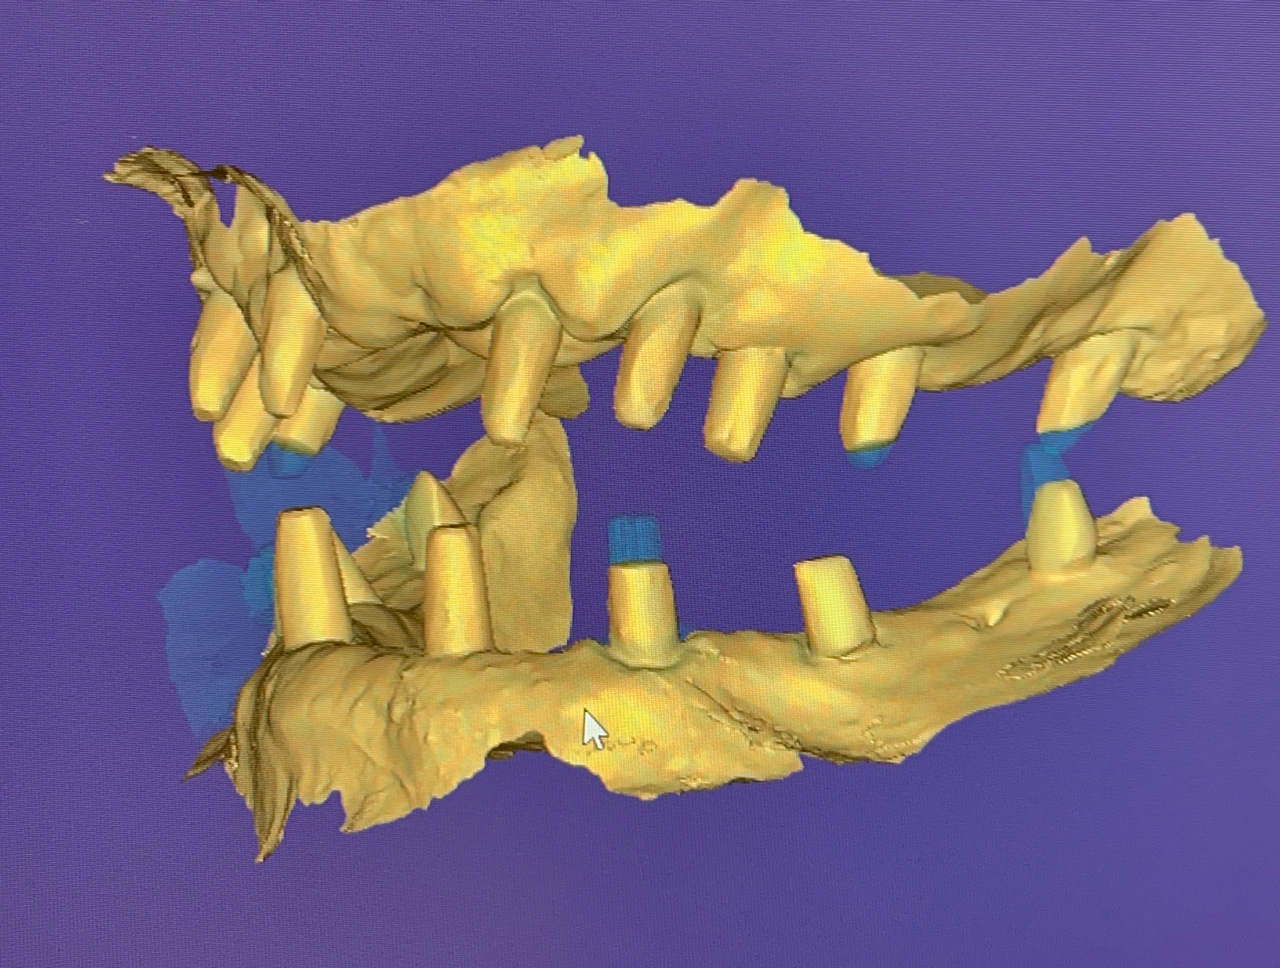

Teljes fogatlanság helyreállítása 2 nap alatt

Teljes fogatlanság helyreállítása 2 nap alatt azonnal terhelhető svájci IHDE implantátumokkal és PMMA műanyag hidakkal. Intraorális szkennerrel vettünk lenyomatot az implantáció után, és erre a digitális mintára készítette el a fogtechnika a hidak digitális tervezését, majd faragta ki műanyagból. Ezt a gyors munkát az azonnal terhelhető implantátumok és a digitális lenyomat, tervezés segítségével tudtuk megcsinálni mindössze 2 nap alatt. Dr. Kelemen Péter és a Symbion Fogtechnika munkája.